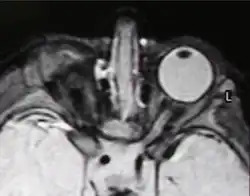

Mikroftalmia (małoocze, ang. microphthalmia, microphthalmos, nanophthalmos, nanophthalmia, z gr. μικρόφθαλμος) – wada wrodzona o charakterze malformacji polegająca na jednostronnym lub obustronnym niedorozwoju gałek ocznych. Przyczyną mikroftalmii, tak jak anoftalmii, jest zaburzenie rozwoju pęcherzyków ocznych[1].

Przeciętna długość gałki ocznej w długiej osi u osoby dorosłej i u noworodka wynosi, odpowiednio, 23.8 i 17 mm. Według The International Clearinghouse for Birth Defects Monitoring Systems w mikroftalmii wymiar rogówki wynosi <10 mm, a wymiar przednio-tylny gałki <20mm[2].